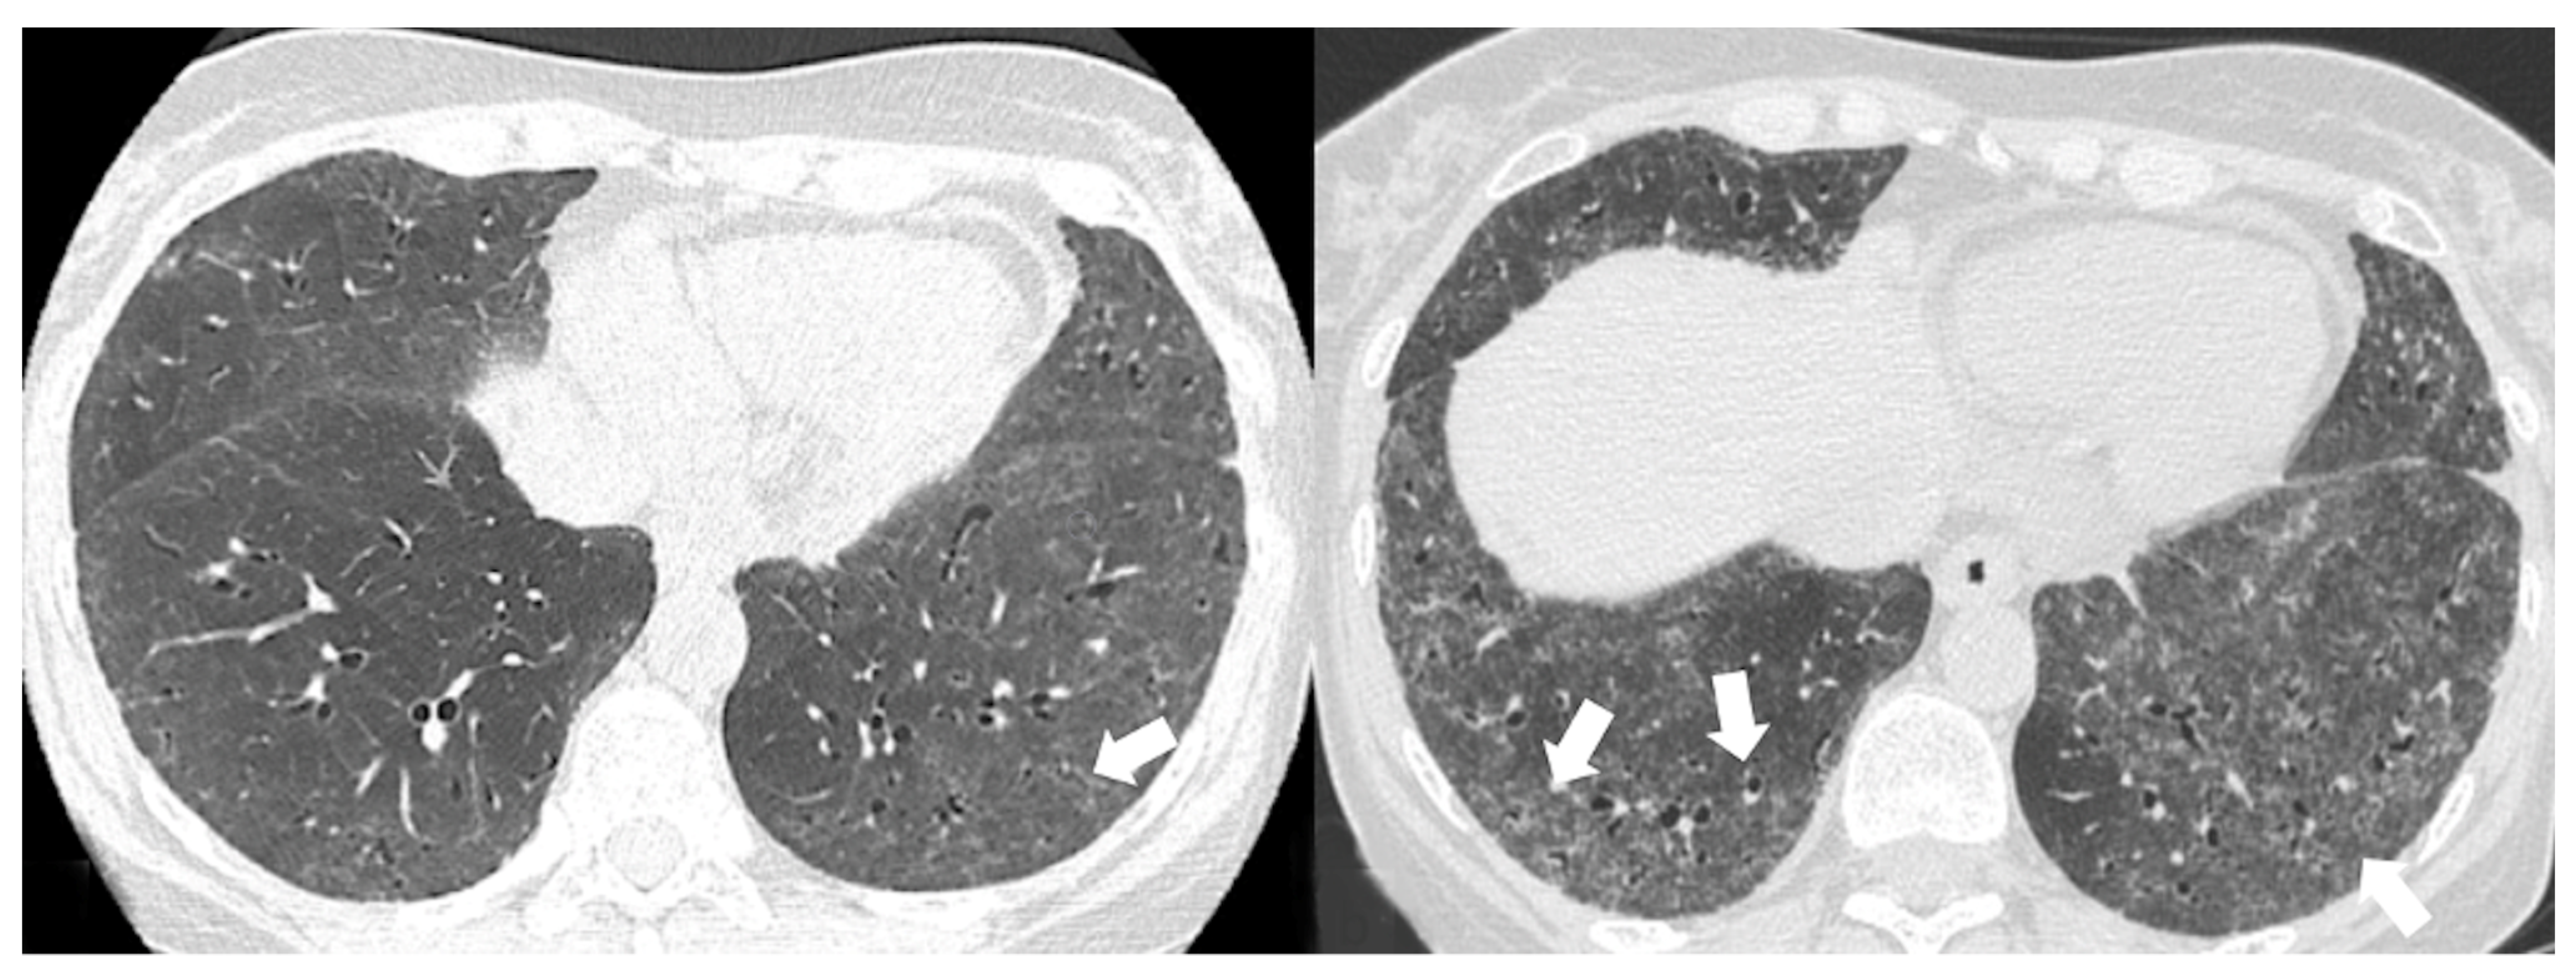

4.2.1. HRCT Findings of Patients with Anti-ARS Abs

4.2.2. HRCT Findings of Patients with Anti-MDA-5 Abs

| Lesions | GGO, reticulations, consolidations | consolidations, GGOs | |

| Distribution | Homogeneous; lower lung lobes, along bronchovascular bundles and lung periphery; loss of volume of lower lobes | Patchy; peripheral lower lobes or along the bronchovascular bundles | |

| CT pattern | NSIP OP NSIP-OP UIP DAD-unclassifiable | 50% 20% 25% 10% +/− | 20% 50% 25% <5% ++ |